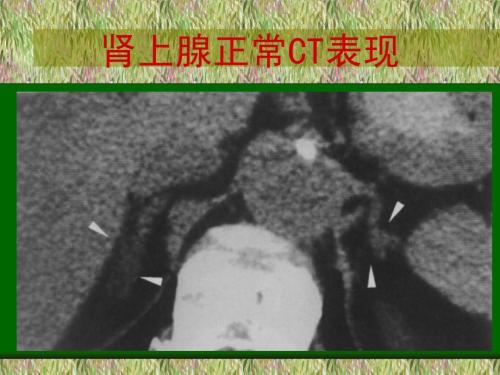

肾上腺肿瘤

2、肾上腺CT ,对于怀疑肾上腺增生或者肾上腺肿瘤的患者可性肾上腺增强CT检查。